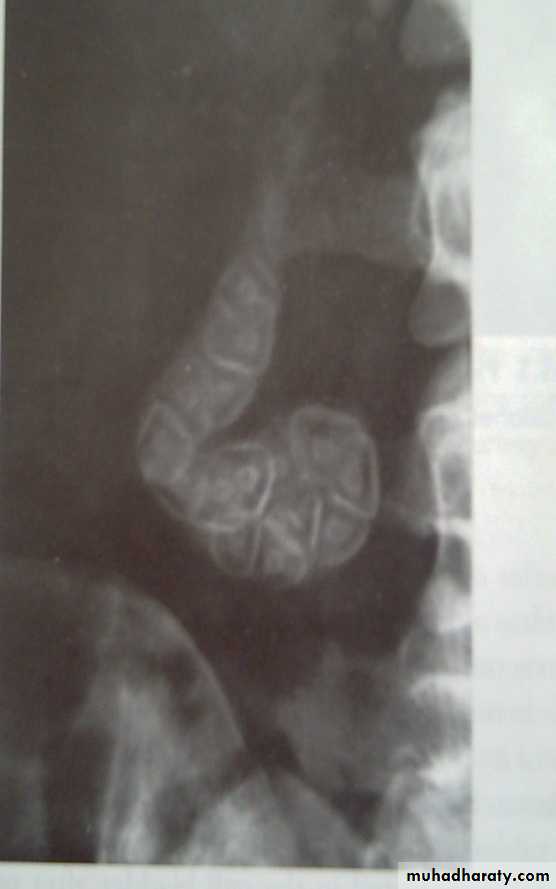

Plain radiogaph:

Radiopaque gall stones in 10%Porcelain GB.. calcified GB..25% CA.

Porcelain GB

Radiopaque Gall stones